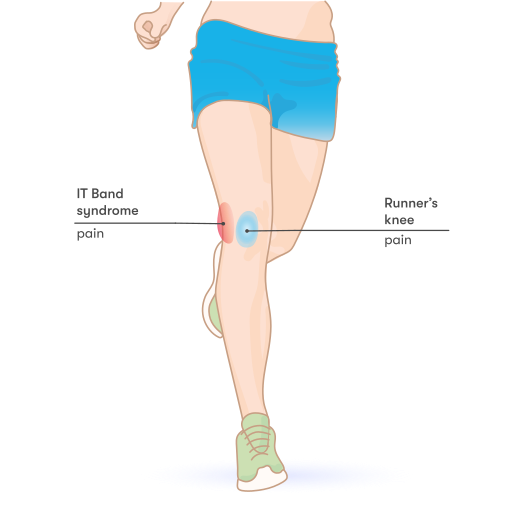

Chondromalacia patella, also known as runner’s knee or patellofemoral pain syndrome, is a common knee condition characterized by the softening, weakening, and damage of the cartilage on the underside of the kneecap (patella). This condition occurs when the patella does not glide smoothly over the femur (thigh bone) during knee movement, causing pain and discomfort.

- Dull, aching pain: Pain in the front of the knee, around or behind the kneecap, often worsens with activities like climbing stairs or after sitting for an extended period. It may affect one or both knees and can radiate to the inner side of the kneecap. This pain typically starts gradually and is often related to activity. Some people may feel pain that’s not located in any specific spot.